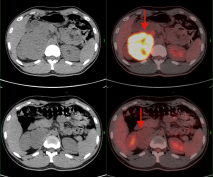

治疗前 治疗后

淋巴瘤治疗前后变化: 弥漫性大B细胞淋巴瘤化疗3程后,腹腔及腹膜后多发肿大淋巴结明显缩小,糖代谢明显减低。

(上两图为:治疗前,下两图为:治疗后)

淋巴瘤治疗前后变化:弥漫性大B细胞淋巴瘤化疗3程后,腹腔机腹膜后多发肿大淋巴结明显缩小,糖代谢明显减低。根据Deauville标准 5PS评分为2分。